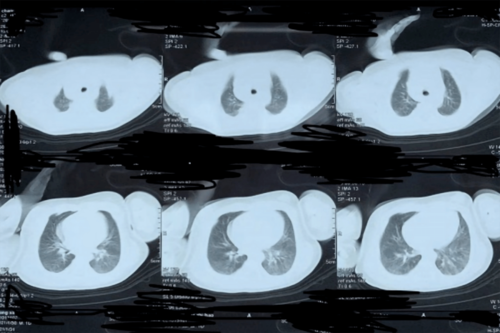

经椎弓根基地部穿刺pkp,出现骨水泥向椎管内漏